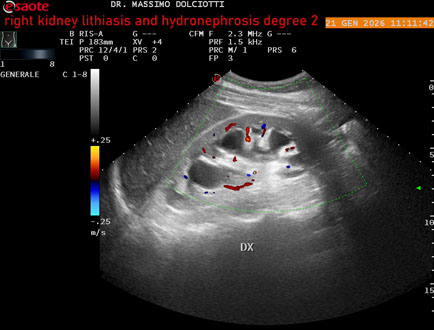

Data inserimento: 22/01/2026

Ecografia del: 21/01/2025

Strumento: Esaote MyLab Eight

Sonda: Convex Multifrequenza 1-8 MHz

Età Paziente: M 27 anni

Motivazione dell'esame: dolore al fianco destro da 3 mesi.

Commento all'esame: le immagini ed il video documentano il rene destro in sede, con ecostruttura disomogenea per evidenza, alla pelvi renale, di immagine iperecogena delle dimensioni di 16,2 mm, con cono d'ombra posteriore, da ricondurre a litiasi ed una formazione simile, di minore entità, al polo inferiore, delle dimensioni di 6,8 mm. Rene dx con diametro longitudinale di 122 mm (v.n. 90-120 mm) x 63 mm e parenchima renale dello spessore di 15 mm (v.n. > 13 mm). Rene dx con idronefrosi di 2° grado.

Conclusioni: litiasi e idronefrosi di 2° grado al rene destro (lithiasis and second-degree hydronephrosis of the right kidney).

In collaborazione: Dr.ssa Marica Manfredi - Ancona, Dr. Ilir Qose - Ancona

Presentazione: Dr. Massimo Dolciotti - Ancona

Elaborazione digitale: Andrea Dini - Ancona